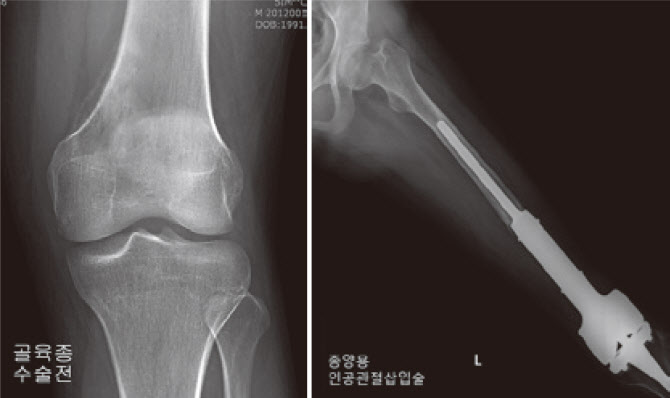

이 밖에도 골연골종(osteochondroma)과 골연골육종(osteochondrosarcoma)이 있는데, 골연골육종은 겨드랑이 연골 종양을 말하며 주로 견갑골, 갈비뼈, 엉덩이뼈에 발생하며 악성 골암의 20%를 차지하며 대부분 중년 이후에 발생한다. 골암은 골암에 비해 골종(osteoma)과 골육종(osteosarcoma)으로 나뉘는데 골종은 골조직의 종양으로 비교적 드문 단일 양성 종양으로 가드너 증후군이나 가족력에 의해 발생하며 전형적인 악성 골종양이다. 모든 뼈 종양의 약 10%에서 출혈과 괴사를 동반합니다. 어떤 경우에는 골 파괴 또는 불규칙한 골 형성 경향이 명백합니다. 전이성 종양은 뼈 이외의 상피 조직에서 발생합니다. 악성 종양이 전이되어 혈액과 골수에 종양을 형성한 경우입니다. 뼈로 전이되기 쉬운 종양에는 유방암, 전립선암, 갑상선암 및 폐암이 포함됩니다.